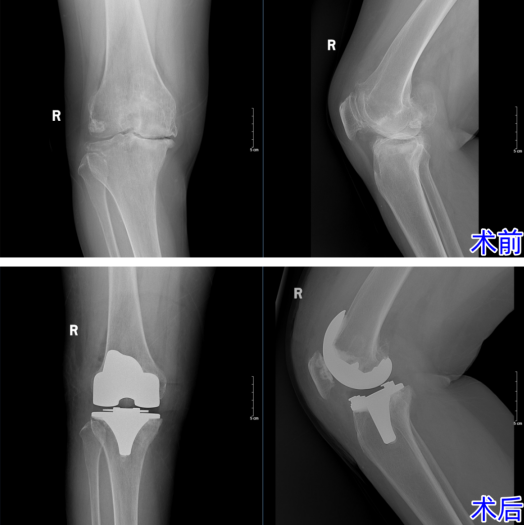

面对这位典型的疑难病例,杨主任团队没有丝毫懈怠。经过缜密的术前评估与个性化方案制定,杨主任亲自操刀,凭借对解剖结构的精准把控与炉火纯青的技术,成功实施了膝关节置换术。术中,病变组织被精准清除,畸形得以矫正,人工关节精准复位。

术后,在医护团队的悉心照料下,王女士迎来了奇迹般的转变。膝关节的僵硬感消失,活动度大幅提升,变形的腿部恢复了正常力线。这场手术,不仅仅置换了一个关节,更置换回了王女士对生活的热爱与尊严。